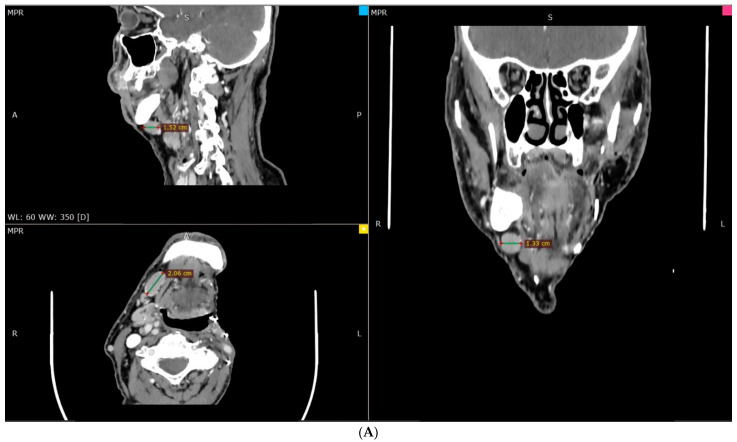

Materials and methods: A case of an 89-year-old man is reported, who initially underwent surgical and complementary treatment for neck squamous cell carcinoma of occult primary and later for tonsillar diffuse large B-cell non-Hodgkin lymphoma.

Results: The second primary was considered a recurrence in the neck of the original cancer of unknown primary, so a new surgical management was decided. The final pathology report described a diffuse large B-cell non-Hodgkin lymphoma.